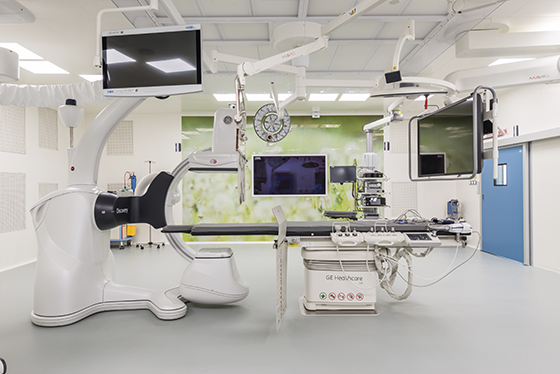

В институте хирургии Hadassah Medical Moscow резекцию желудка выполняют высококвалифицированные хирурги, врачи с мировым именем и уникальным опытом проведения операций. Осуществляется хирургическое лечение с применением экспертного оборудования, передовыми методами и наиболее щадящими техниками. Мы внедрили в свою клиническую практику мировые достижения современной хирургии и предлагаем инновационные решения. Если вам нужна помощь, доверьтесь группе врачей Hadassah Medical Moscow – у нас есть всё, чтобы добиться желаемого лечебного результата и восстановить ваше здоровье!

- Современный стационар с высококлассным оснащением. У нас инновационное хирургическое оборудование, экспертные лапароскопы, эндоскопы, применяются новейшие хирургические инструменты.